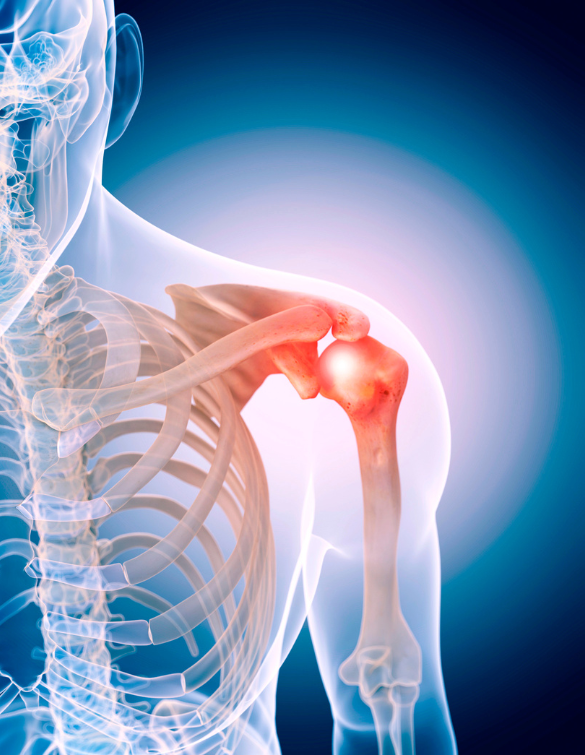

Shoulder Fracture

The shoulder is a sophisticated joint made up of the scapula (shoulder blade), the humerus (upper arm bone), and the clavicle (collarbone). Various muscles, ligaments, and tendons surround all these bones. The shoulder is the most mobile joint which allows you to place your arm and hands in a variety of positions. As the most mobile joint, it is highly prone to injuries and problems.

A fractured shoulder or broken shoulder can be either displaced or non-displaced. When the broken pieces are still in their anatomic position, it is described as a non-displaced fracture. Displaced shoulder fracture requires restoring the shoulder to its normal anatomy. Proximal humerus fracture, fractured scapula, and fractured clavicle are the different types of shoulder fractures.

Shoulder fractures are the traumatic events resulting from a fall on the shoulder, accidents, contact sports, etc. The shoulder is a complex joint connecting the upper end of the humerus with glenoid (socket of capsule). Any disturbing event or rupture in these parts results in fractures and can affect the functioning of the shoulder.